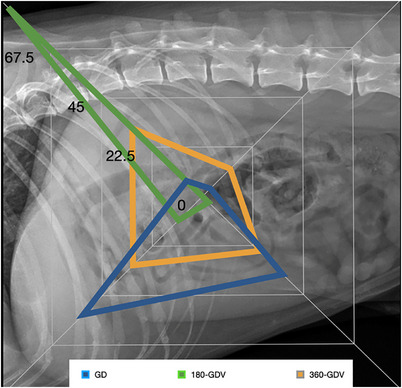

Gastric dilatation and volvulus (GDV) is a life-threatening emergency that requires urgent intervention. Radiographic features associated with 360-GDV in dogs have not been investigated. The aim of this retrospective observational study is to describe radiographic features and clinical variables in dogs affected with 360-GDV and to report agreement rates between different radiologists. We also report the sensitivity and specificity of radiographs to diagnose 360-GDV in dogs. Confirmed 360-GDV cases were retrieved, and the radiographic findings were compared with dogs presenting with gastric dilatation (GD) and 180-GDV. Images were reviewed and graded by three blinded board-certified radiologists. A total of 16 dogs with confirmed 360-GDV were identified. The median age was 10 years old (2-13 years). The sensitivity for detection of 360-GDV ranged between 43.7% and 50%, and the specificity between 84.6% and 92.1%. Interobserver agreement on final diagnosis was substantial (Kappa = 0.623; 0.487-0.760, 95% CI). The highest agreement rate was in cases of 180-GDV (87%), followed by the GD cases (72%) and 360-GDV (46%). Severe esophageal distension and absence of small intestinal dilation were the only radiographic features specifically associated with 360-GDV. A similar pyloric position was found between GD and 360-GDV. Additional radiographic variables that could help differentiate GD from 360-GDV include the degree of gastric distension and the peritoneal serosal contrast. Two cases with 360-GDV were misdiagnosed by the three radiologists as GD. In conclusion, radiographically, 360-GDV cases can reassemble GD and vice versa. Radiologists and clinicians should be aware of the low sensitivity of radiographs for the detection of 360-GDV.

胃扩张和胃内卷(GDV)是一种危及生命的急症,需要紧急干预。目前尚未研究过与犬 360-GDV 相关的放射学特征。这项回顾性观察研究旨在描述受 360-GDV 影响的犬的放射学特征和临床变量,并报告不同放射科医生之间的一致率。我们还报告了诊断 360-GDV 的敏感性和特异性。我们对确诊的 360-GDV 病例进行了检索,并将其影像学结果与胃扩张(GD)和 180-GDV 病例进行了比较。由三位具有盲人资格的放射科医师对图像进行审查和分级。共有 16 只狗确认患有 360-GDV。中位年龄为 10 岁(2-13 岁)。检测 360-GDV 的灵敏度介于 43.7% 和 50% 之间,特异性介于 84.6% 和 92.1% 之间。观察者之间对最终诊断的一致性很高(Kappa = 0.623; 0.487-0.760, 95% CI)。一致率最高的是 180-GDV 病例(87%),其次是 GD 病例(72%)和 360-GDV 病例(46%)。食管严重扩张和无小肠扩张是与 360-GDV 特别相关的唯一影像学特征。GD 和 360-GDV 的幽门位置相似。有助于区分 GD 和 360-GDV 的其他影像学变量包括胃扩张程度和腹膜浆膜对比度。有两例 360-GDV 病例被三位放射科医生误诊为 GD。总之,从影像学角度看,360-GDV 病例可与 GD 病例重合,反之亦然。放射科医生和临床医生应该意识到,放射线检查对 360-GDV 的检测灵敏度较低。